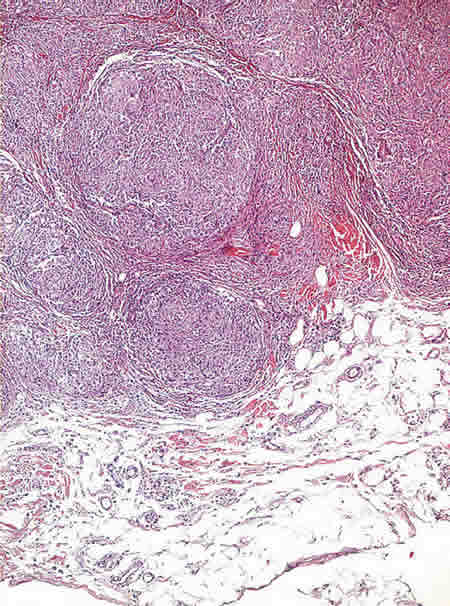

Fig. 2: Granulomas no necrotizantes en dermis profunda e hipodermis. (H-E x200).